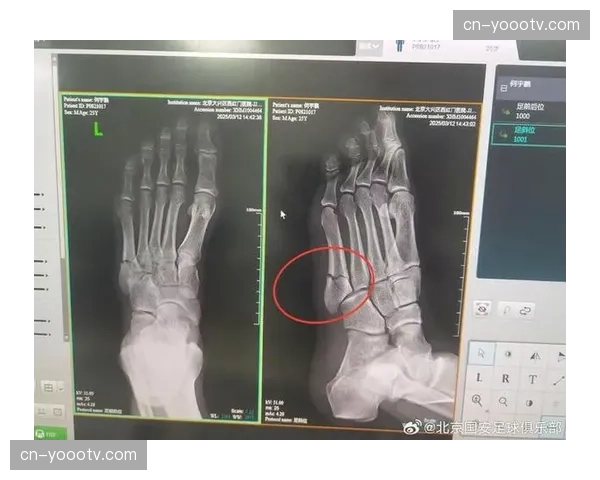

何宇鹏跖骨骨折康复周期较长 右路防守深度需要补充

何宇鹏的伤病成为中超2026赛季4月的一大焦点。在近期的训练中,这位大连人队的主力右后卫不幸遭遇跖骨骨折,初步诊断显示康复周期较长。这一突发情况不仅让球队在右路防守上面临深度不足的问题,也对大连人队的...